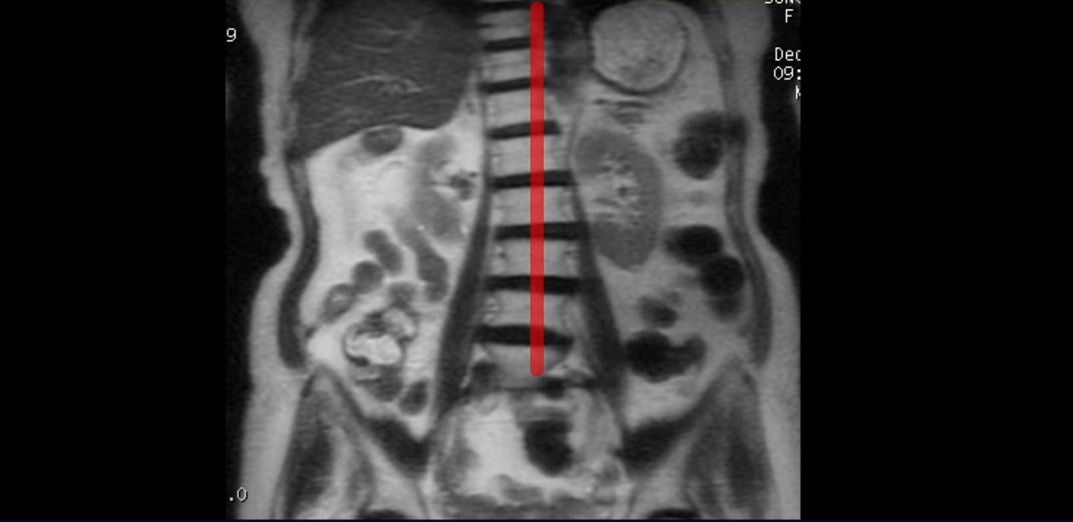

그런데도 아직도 많은 분들이 근육의 중요성을 모르고 신경치료만 하고 있습니다. 하지만 근육과 신경은 떼놓고 생각할 수가 없습니다. 근육이 나빠지면 신경 눌림이 심해져서 협착증 증상이 더 악화되고, 또 신경이 눌리면 근육도 더 빨리 나빠집니다. 반대로 근육이 좋아지면 신경 눌림이 줄어들고 협착증이 좋아집니다. 신경이 눌린다고 하니까 신경 눌림을 풀어주는 수술만 생각을 하시는 분들이 많은데 근육이 좋아져서 허리를 잘 지지해주면 신경이 덜 눌립니다. 이 환자분도 근육이 얼마나 안 좋은 지는 이분 척추가 얼마나 휘어있는 지만 봐도 알 수 있습니다. 보시다시피 근육들이 척추를 잘 지지하지 못하니까 척추가 심하게 휘어있습니다.